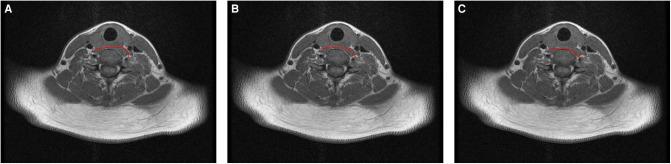

METHODS

The current study enrolled 30 patients who suffered from central spastic paralysis of an upper limb and who underwent contralateral cervical 7 nerve transfer via Prof. Xu's prespinal route through the anterior edge of the contralateral longus colli. MRI images were used to analyze the route length, vertebral artery exposure, and contralateral cervical 7 nerve included angle. Three prespinal routes were virtually designed and analyzed. The selected optimal route was applied to another 50 patients with central spastic paralysis of an upper limb for contralateral cervical 7 nerve transfer.

方法

本研究纳入30例上肢中枢性痉挛性瘫痪患者,这些患者通过徐教授的经对侧颈长肌前缘的椎前入路接受了颈7神经交叉移位手术。利用MRI图像分析入路长度、椎动脉暴露情况以及对侧颈7神经夹角。虚拟设计并分析了三条椎前入路。将选定的最佳入路应用于另外50例上肢中枢性痉挛性瘫痪患者进行颈7神经交叉移位。